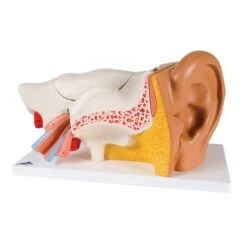

Rolyan Biodynamic Flexion/Extension Component

Includes components for the biodynamic splinting of one finger:

- Finger wraps with monofilament

- Line guide

- Tension-adjustable connecting piece

- Two tension adjustment strips